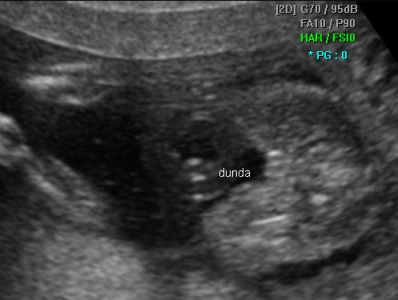

Потврда на женско бебе